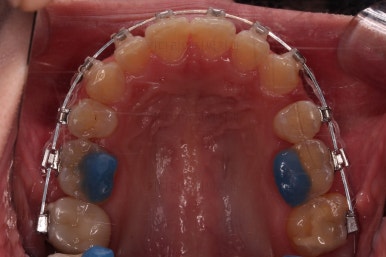

초진 시 입안의 모습입니다.

전반적으로 치열이 삐뚤고, 특정 앞니는 톡 튀어나가 미적으로 좋지 못한 상황이었습니다.

이갈이, 이악물기 습관도 있어서 앞니는 삐뚤어진 채로 치아가 많이 갈려있는 상황이었습니다.